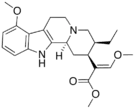

There are a number of broad classes of opioids:[260]

- Semi-synthetic opioids: created from either the natural opiates or morphine esters, such as hydromorphone, hydrocodone, oxycodone, oxymorphone, ethylmorphine and buprenorphine;

Opium alkaloids and derivatives

Semi-synthetic alkaloid derivatives